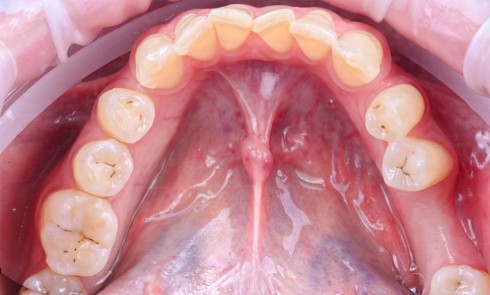

Le patient

- 70 ans

- Pas d’antécédents médicaux

- Ne fume pas

- Hygiène correcte

L’implant

- Site 23

- Mis en place il y a 12 ans